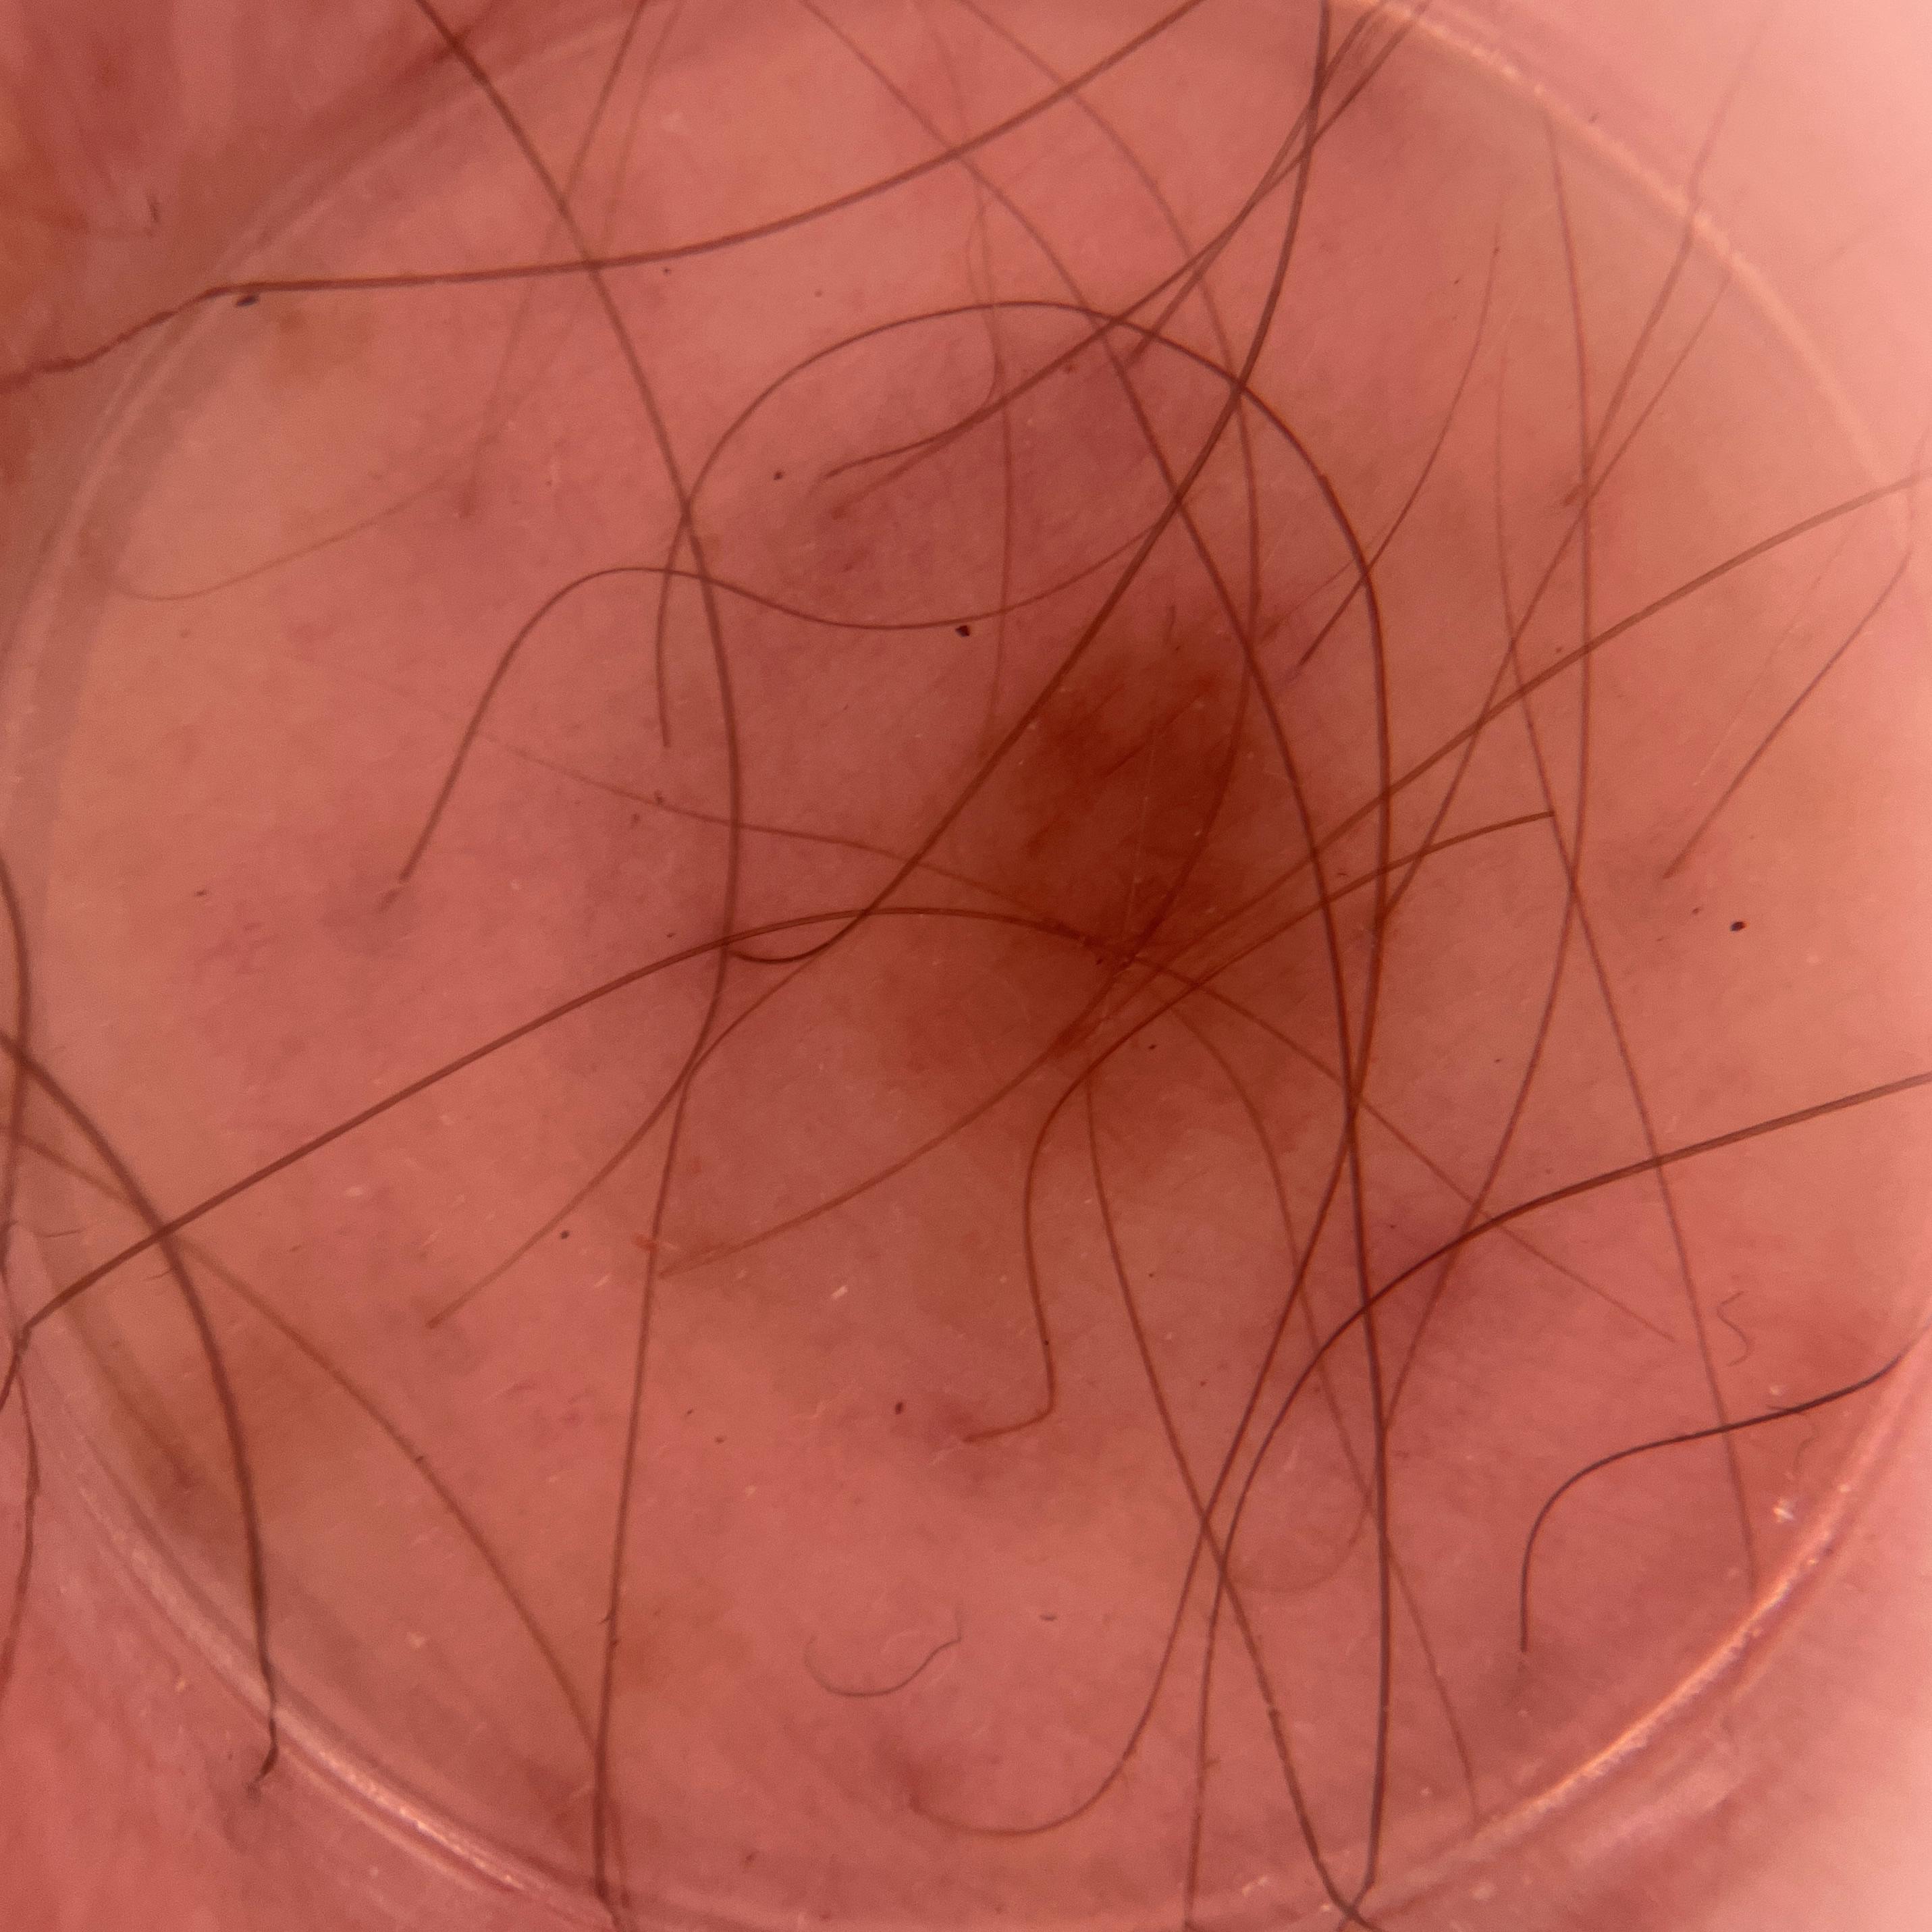

ISIC_8917580

Clinical

Field Value

acquisition_day 361

age_approx 60

anatom_site_1 Lower extremity

anatom_site_general lower extremity

concomitant_biopsy False

diagnosis_1 Benign

diagnosis_confirm_type single image expert consensus

family_hx_mm True

image_manipulation instrument only

image_type dermoscopic

lesion_id IL_4139461

patient_id IP_1989106

personal_hx_mm True

sex male